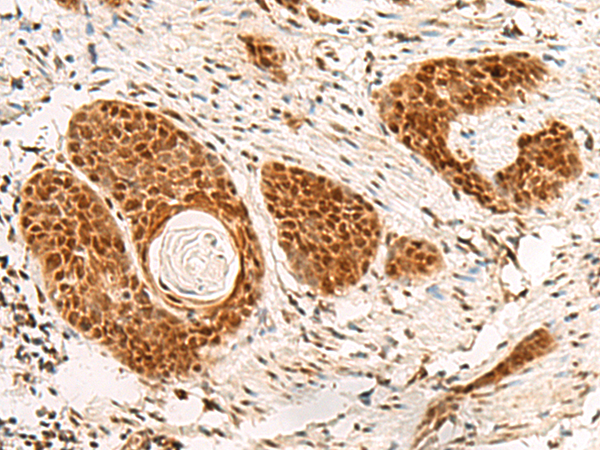

分类: 科研抗体货号: P09961别名: TGC1; TSGA3; SPGFX2应用: IHC反应种属: Human